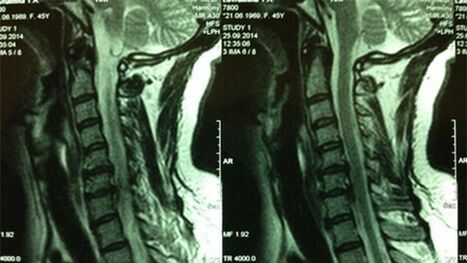

- X -ray of cerrvical sector;In the initial phase of the procedure, the MRI by the Cervical Department will be informative - will provide high visualization of solid and soft tissues - the situation of interfood drives, the presence of osteophytes, deformation, nervous roots and blood vessels;Will assess the state of ligaments, muscles, bone tissues;